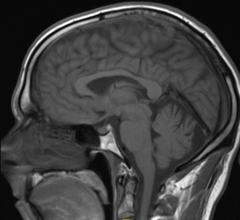

School-age football players with a history of concussion and high impact exposure undergo brain changes after one season of play, according to two new studies conducted at UT Southwestern Medical Center in Dallas and Wake Forest Baptist Medical Center in Winston-Salem and presented at the 2017 annual meeting of the Radiological Society of North America (RSNA), Nov. 26-Dec. 1 in Chicago.

Although targeted therapies have produced dramatic advances in the ability to control some types of advanced lung cancer, growth of the disease in the brain remains a major problem. Radiation is often used to treat deposits in the brain, but the best technique to deliver radiation can be controversial. Whole-brain radiation therapy, as its name suggest, treats the entire brain but can be associated with notable cognitive side effects. Another strategy, radiosurgery, directs highly-focused radiation only to the sites of metastasis, largely sparing the normal brain.

Information from brain magnetic resonance images (MRIs) can help identify people with attention deficit hyperactivity disorder (ADHD) and distinguish among subtypes of the condition, according to a study appearing online in the journal Radiology.